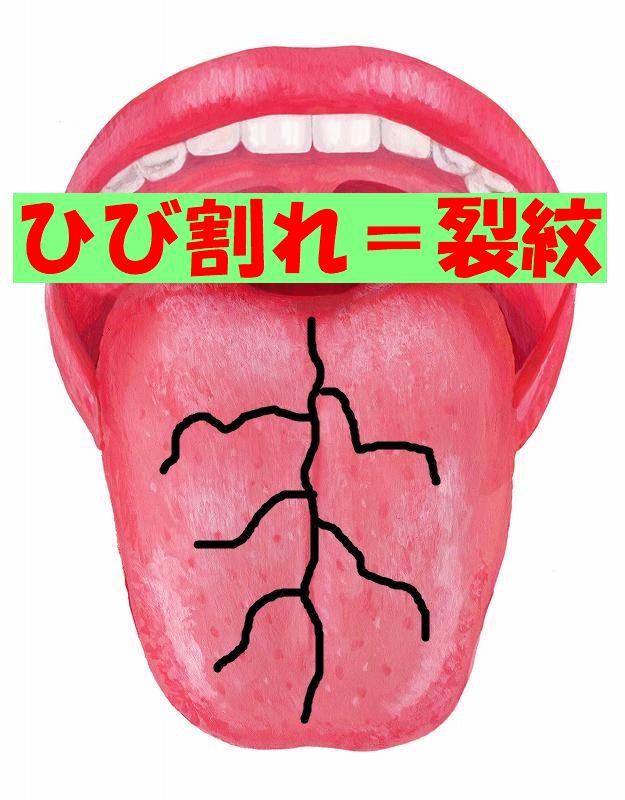

舌の{ひび割れ}=裂紋すみれ漢方施薬院薬局のブログ。

舌のひび割れはなぜ起きる?原因と対処法について徹底解説! – ココシカ。

病気サイン?舌がひび割れる4つの原因。溝状舌・ドライマウスはどう治す?病院は何科?Medicalook メディカルック。

舌のひび割れはなぜ起きる?原因と対処法について徹底解説! – ココシカ。